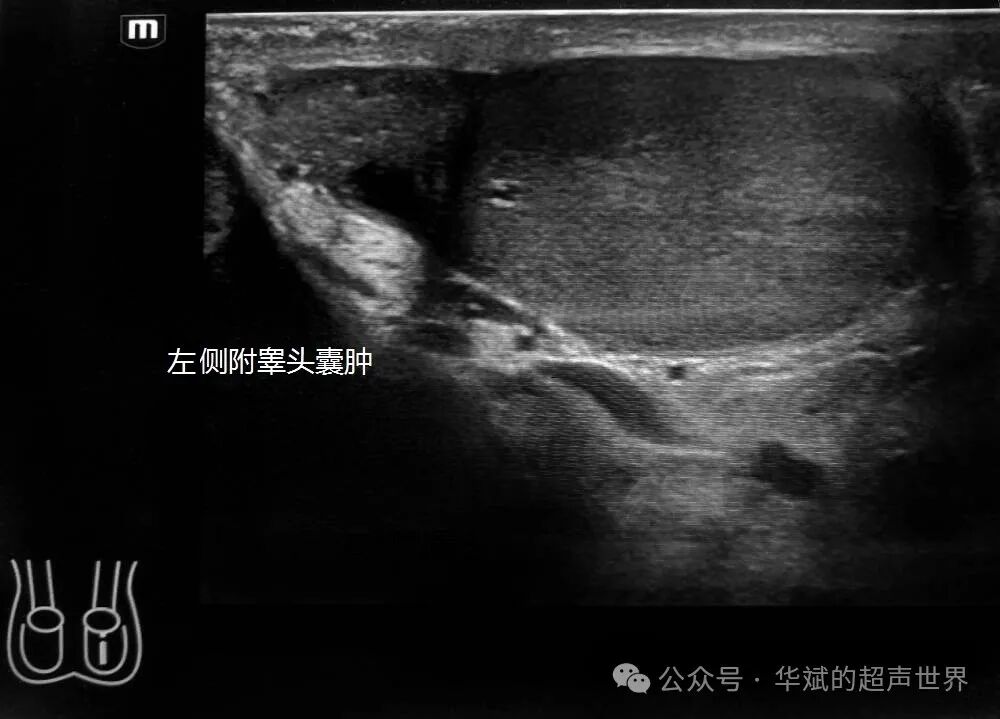

youyuanzhiren 问:华斌老师您好!最近遇见一个夜间急诊病人,27岁,腹股沟区疼痛难忍来就诊的患者,查看泌尿系彩超是正常的,血常规,尿常规没问题。超声检查双侧睾丸未见异常,左侧附睾头囊肿,右侧附睾头可见多发的强回声团,后伴声影和快闪伪像,这种考虑结石吗,后面随访说医生开了点止痛跟消炎药回家吃了第二天就没事了,请老师您帮忙看看!

附睾内的结石较少见,也偶尔有输精管和精囊内的游离结石的报道,尽管这些结构的壁的钙化更为常见。附睾小结石可能是由于精子的凝集和随后的钙化,或慢性炎症过程的结果。

通常情况下附睾结石是无症状的。部分附睾结石可能与附睾炎有关,会伴有附睾睾丸疼痛的症状。本例患者的腹股区疼痛可能与附睾炎的急性发作有关,不过由于提供的图片相对比较少,不好确定。